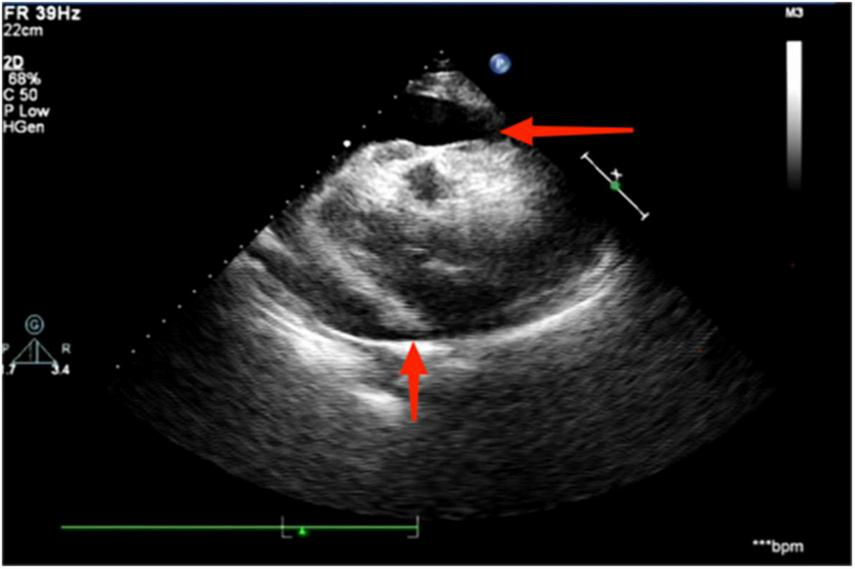

The electrocardiogram (Figure 1) suggested a sinus heart rate with low voltage in the limb leads. The patient’s laboratory data at admission are shown in Table 1. Echocardiography indicated moderate to severe pericardial effusion (Figure 2), and echo-free areas were seen in the pericardial cavity. The diastolic fluid width was measured as 14 mm in the anterior wall of the right ventricle, 16 mm in the posterior wall of the left ventricle, 19 mm in the lateral wall of the left ventricle, and 20 mm in the apical part of the left ventricle. A bedside color doppler ultrasound showed bilateral pleural effusions. After admission, the patient had a fever intermittently, with a temperature of up to 38.3°C without chills and shivering. The patient’s temperature was elevated within 24 h of admission, meaning that the possibility of community-acquired pneumonia could not be excluded. After blood cultures were retained, the patient was also given empirical anti-infective treatment with moxifloxacin. However, as the patient’s improvement in relevant tests was considered not to exclude tuberculosis, the use of fluoroquinolones alone should be avoided, and the patient’s moxifloxacin was discontinued and changed to ampicillin. The patient’s blood culture later indicated no bacterial growth. A computed tomography (CT) scan of the lungs revealed sporadic inflammation in both lungs, inflammatory nodules in the upper left and lower right lung lobes, calcification in the upper left lobe (Figure 3), and bilateral pleural effusions. Furthermore, the mediastinal lymph nodes were enlarged and partially calcified. Pericardiocentesis and drainage were used to relieve the patient’s symptoms, such as chest tightness and shortness of breath. The patient’s pericardial effusion was hematogenous, with routine results as follows: protein 53.96 g/L; Reye’s test positive; total erythrocyte count 214300.00 × 106/L; total leukocyte count 3762.00 × 106/L; percentage of single nucleated cells 84%; adenosine deaminase (ADA) 32.0 U/L; lactate dehydrogenase (LDH) 326 U/L; and carcinoembryonic antigen (CEA) 0.47 ng/ml.

FIGURE 2

Echocardiography suggests the presence of a moderate to large pericardial effusion, as indicated by the red arrowhead.